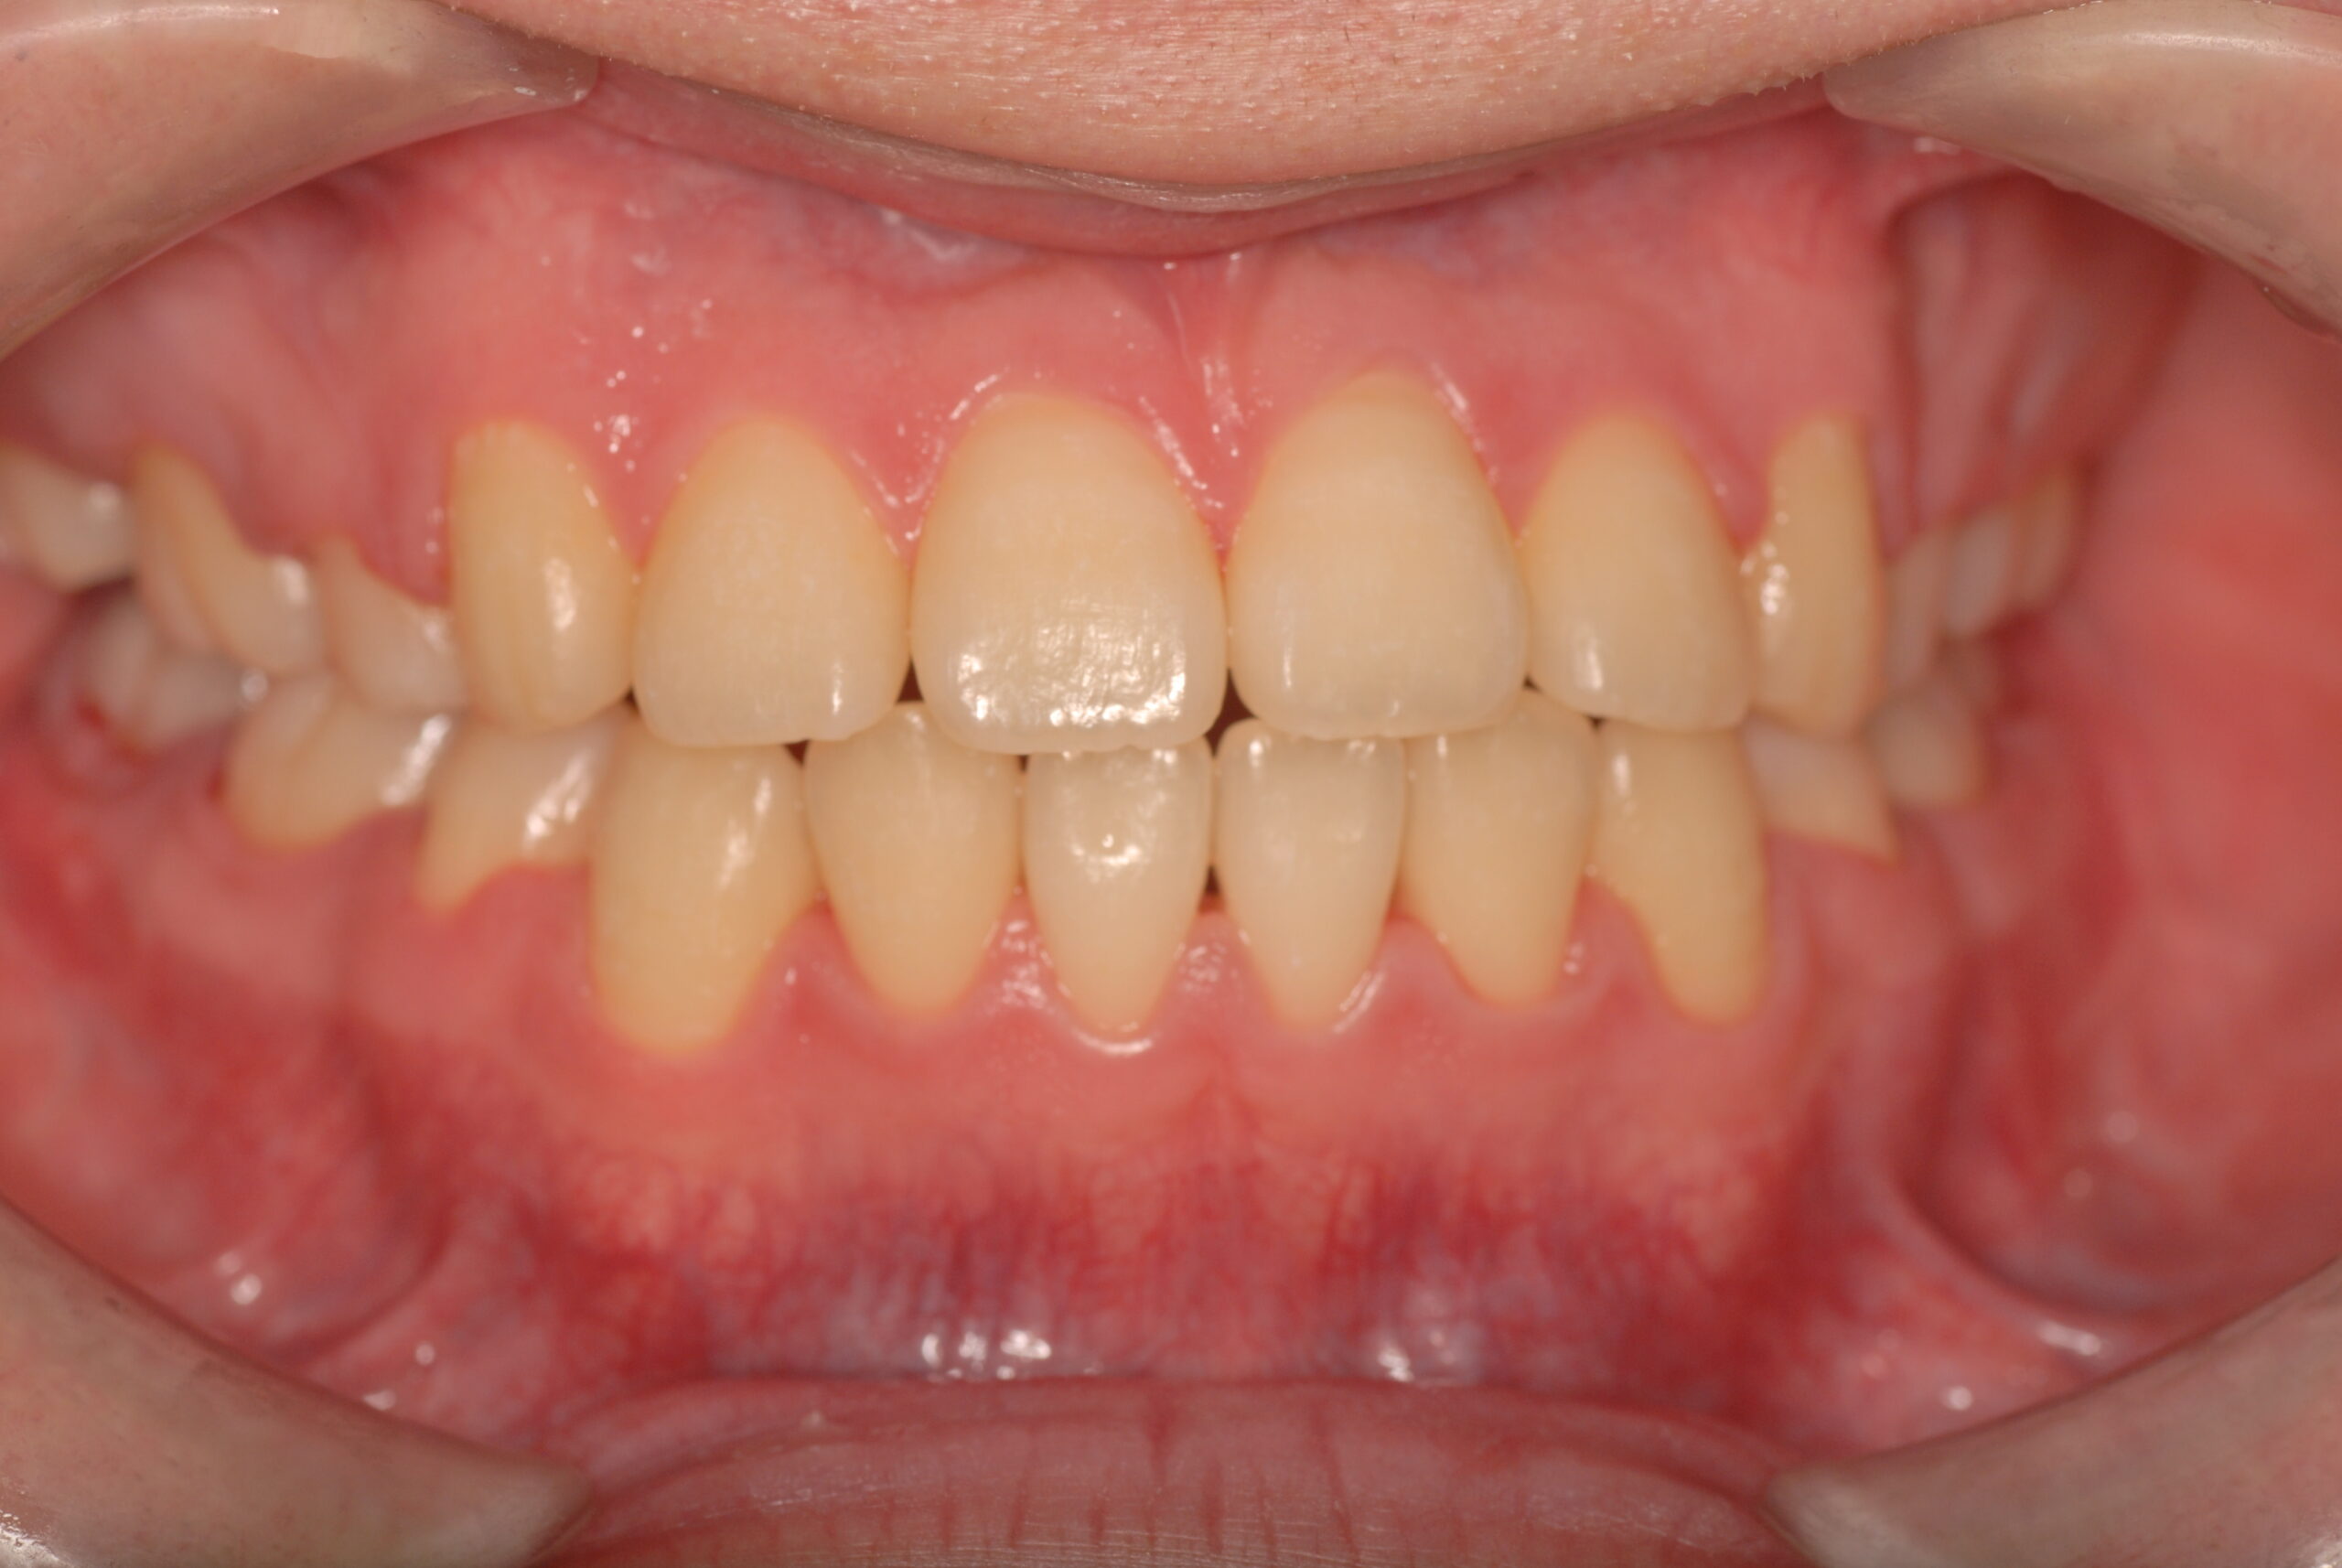

After

- 骨格性下顎前突症、下顎骨左偏位、叢生、 顎変形症として、外科的矯正術を計画。 叢生、右側第2大臼歯鋏状咬合。 上下顎第一小臼歯を抜歯し、抜歯空隙を利用し叢生を改善し、上下顎それぞれ歯列を整列し、矯正治療中に病院歯科口腔外科にて外科手術(近郊の病院歯科口腔外科にて、口の中から手術、2週間入院)により下顎骨の後退と左偏位の改善をし、適切なオーバージェット、オーバーバイトを付与する。